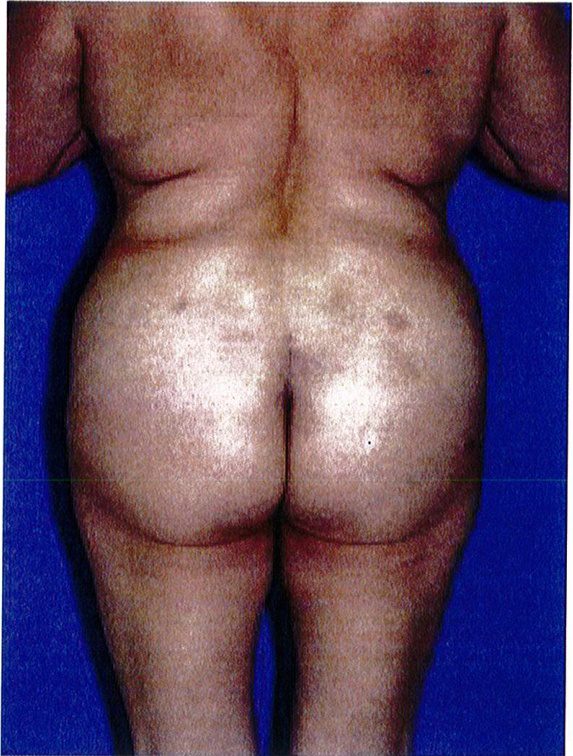

Sự tương tác của 4 tổ chức này mang lại cho vùng mông một hình dáng đặc trưng cụ thế (hình 1A). Để đơn giản hóa chủ đề phức tạp này, hãy tưởng tượng cơ thể là một cấu trúc có thể tháo rời. Khi tách cơ ra thì phần còn lại là khung xương, mỡ và da, có thể gọi chung là khung (Hình 1B).

Hình 1. (A) Hình thể toàn bộ vùng mông phụ thuộc vào khung xương, cơ mông lớn, vị trí và lượng mỡ dưới da, độ căng của da. (B) Khung mông, với cơ môna lớn đã được tách ra.

Over rall Buttock Shape : Hình thể toàn bộ vùng mông Gluteal muscle: Cơ mông Gluateal muscle(gluteal shape): Hình dạng cơ mông Frame: Khung